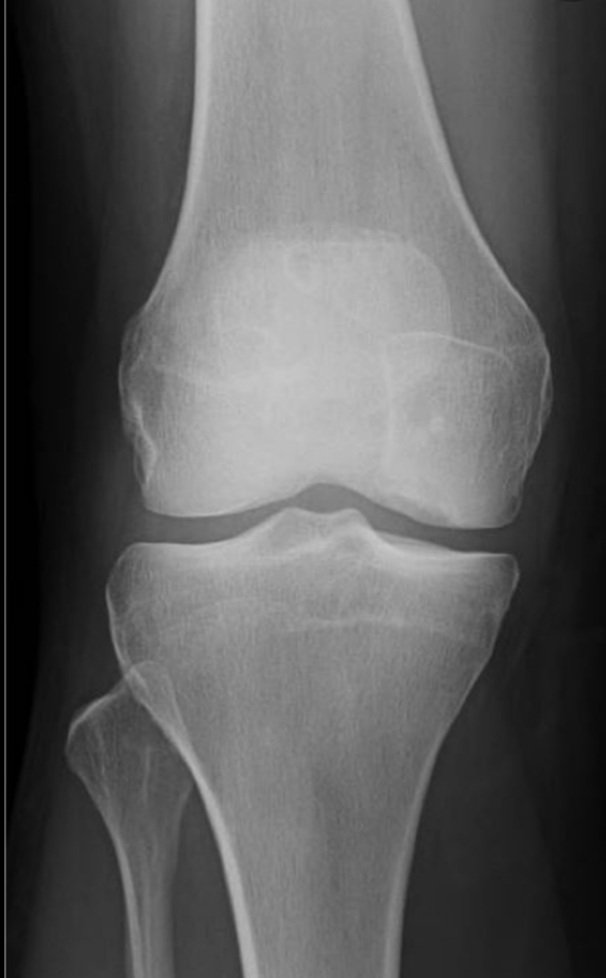

٤- ينصح بعمل أشعه سينية للركبة المصابة لبحث عن كسور قد تحدث في الإصابة.